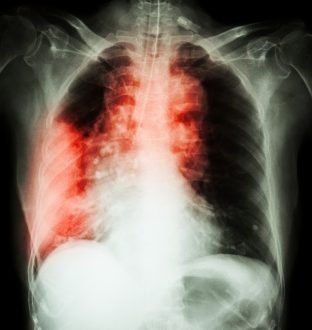

kanker paru

pic : freedigitalphotos.net